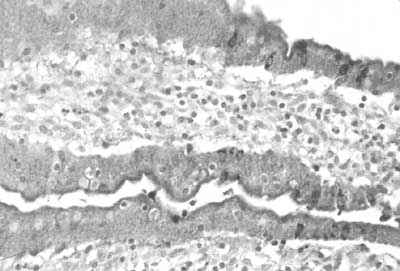

FIGURE 28. Indirect immunoperoxidase staining of colon from an infected animal with anti-rinderpest polyclonal antibody showing the location of virus antigen (Photo: P. Wohlsein)

FIGURE 29. Indirect immunoperoxidase staining of liver tissue from an infected animal with anti-rinderpest polyclonal antibody showing virus antigen in the bile duct epithelium (Photo: P. Wohlsein)